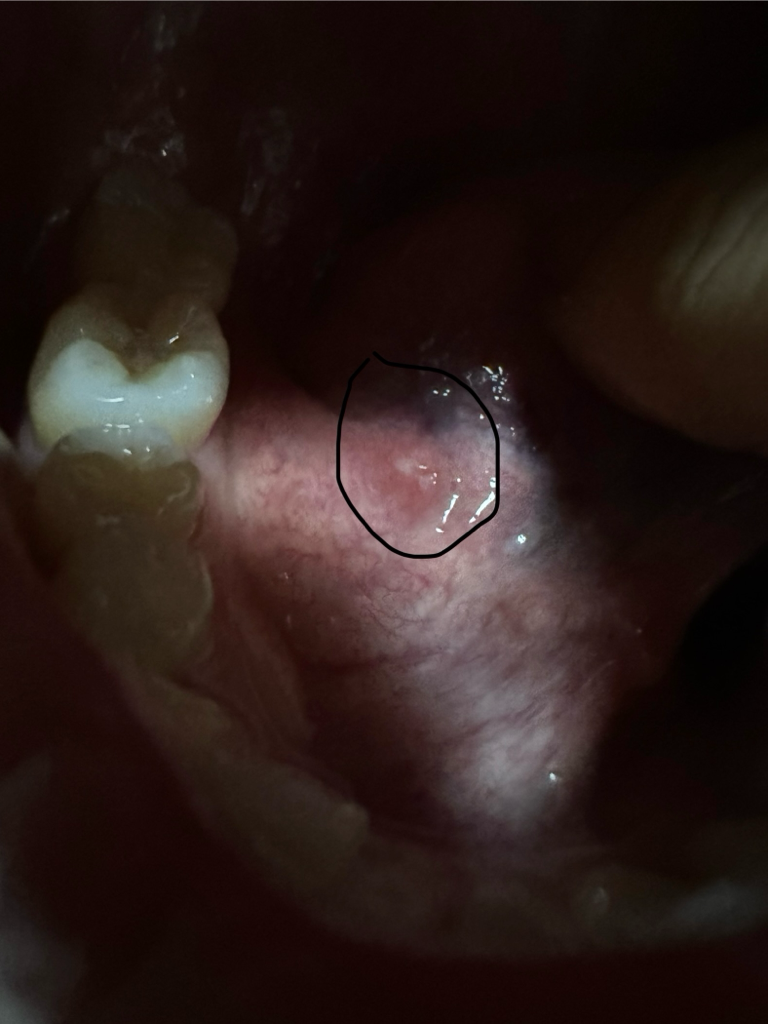

혀 밑에 통증이 자꾸 느껴져서 봤더니 흰색 염증이 있어요.

사진보시면 흰색 염증같은 거 있는 곳에 통증이 있어요.

동그라미 쳐놓은거는 알보칠바르기전이고 동그라미 없는거는 알보칠을 바른 후 입니다

• 1번 째 사진